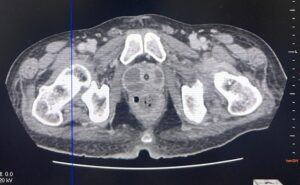

Realizou os exames de imagem abaixo: